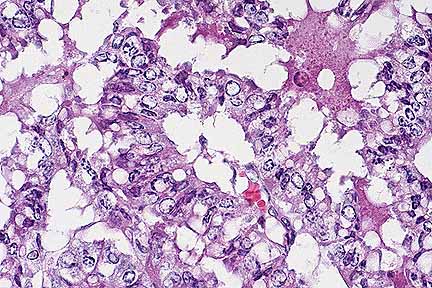

Higher magnification of the neoplasm above. Note tubular formation and marked nuclear atypia. (HE, 400X, 55K)

Contributor's Diagnosis and Comments: Mammary Gland: Adenocarcinoma, intraductal and papillary, multiple, New Zealand White rabbit.

Mammary gland adenocarcinomas of rabbits are relatively uncommon. The literature from 1911 to 1962 includes 36 cases of primary mammary gland adenocarcinomas of rabbits. This tumor occurs most often in multiparous females older than three years. In theory, preexisting endocrinological disturbances sensitize the glandular epithelium to the carcinogenic effects of estrogen. There may be a genetic component as well, since the majority of reported cases have occurred in Belgian and English breeds.

The invasive (intraductal) form is often, but not always, preceded by slowly progressive cystic and papillomatous changes, and is the eventual outcome of the papillomatous stage. Mammary adenocarcinomas usually develop independently of the more common uterine adenocarcinoma of rabbits, although cystic mammary changes occur in association with about 25% of uterine adenocarcinomas. This rabbit had diffuse, cystic endometrial hyperplasia, considered by some to be an antecedent to uterine carcinoma. Metastasis to the lungs, abdominal organs, lymph nodes and bone marrow have been reported in approximately 20% of cases. In this case there were no gross or microscopic metastases. Testicular adenocarcinoma also has been reported in rabbits.

AFIP Diagnosis: Mammary gland: Adenocarcinoma, mammary, New Zealand White rabbit, lagomorph.

Conference Note: Other changes commonly seen in association with mammary adenocarcinoma in rabbits include vacuolar change of adrenal cortical cells, pituitary gland hyperplasia, and cystic hyperplasia of uterine endometrial glands. These three changes are consistent with hyperestrinism; however, neither uterine or mammary adenocarcinoma have been experimentally induced by the administration of estrogen.

As in rabbits, familial risk factors and estrogen imbalances have also been implicated in human breast carcinoma. Genetic predisposition has been associated with a small locus in chromosome 17q21, named BRCA1 (breast carcinoma 1). This gene has also been linked to ovarian cancer. The role of estrogen in development of human breast carcinoma is not completely understood; however, excess estrogens have been associated with an increased breast cancer risk. In humans, normal breast epithelium possesses estrogen and progesterone receptors, as do some types of human breast cancer. Human breast cancer cells have also been shown to produce growth factors such as transforming growth factor-à, epithelial growth factor, fibroblast growth factor, platelet derived growth factor, and transforming growth factor- . These growth factors are believed to be involved in an autocrine mechanism of tumor progression. Production of these growth factors is dependant on estrogen and the interactions of estrogen receptors on cancer cells. Circulating hormone and the autocrine growth factors are also presumed to be involved in tumor progression.